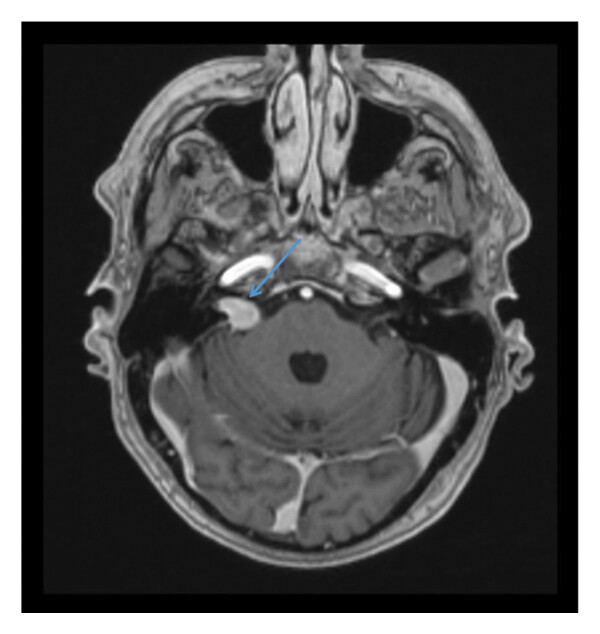

Пациенту была проведена аудиограмма, которая подтвердила прогрессирующее снижение слуха справа, и лабораторные исследования: общий и биохимический анализ крови, содержание витамина B12, фолиевой кислоты, цинка и тиреотропного гормона (без отклонений). На МРТ головы было обнаружено образование в области передней части турецкого седла и ската черепа, без компрессии зрительного перекреста (рис.1).

Рисунок 1. МРТ-снимок головного мозга в саггитальной плоскости. Синяя стрелка указывает на образование в передней части турецкого седла без компрессии зрительного перекреста с инвазией в кавернозные синусы.

Дифференциальный диагноз включал аденому гипофиза, хордому или метастатическое поражение. С этой целью у пациента был исследован гормональный профиль (без отклонений) и проведено офтальмологическое обследование (без отклонений). КТ грудной клетки, брюшной полости и таза также не выявила злокачественных новообразований. Повторная МРТ выявила вестибулярную шванному справа размером 1,6 см и подтвердила наличие образования в передней части турецкого седла (рис. 2).